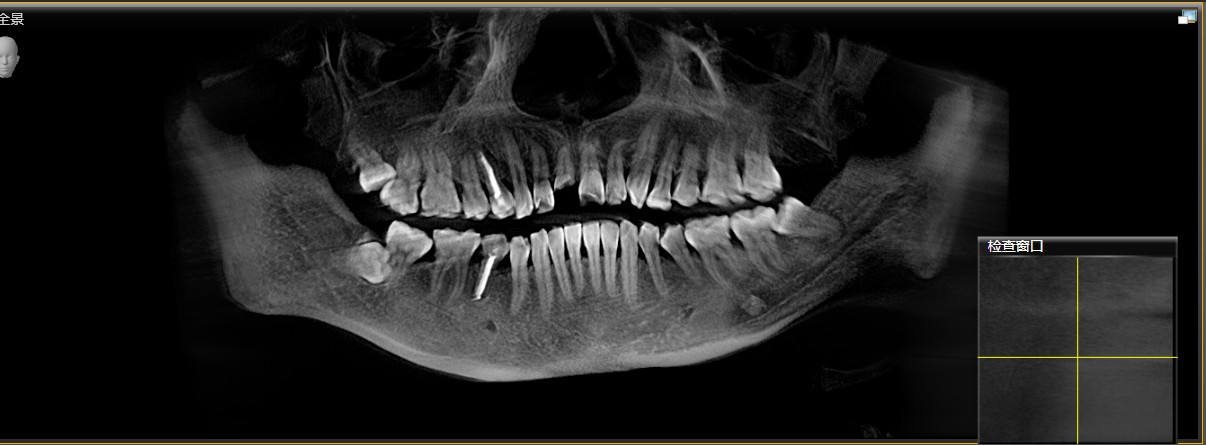

患者右上中切牙外伤导致冠根折,腭侧折面至骨下2mm,需要拔除患牙,x片显示唇腭侧牙槽骨完整,唇侧牙槽骨厚度1.5mm,根尖区剩余牙槽骨也有8mm,符合即拔即种即修复基本条件,患者知情同意下,术前两小时CEREC数字化扫描,设计种植导板,术前准备,拔除患牙,种植导板精密就位,种植窝完成制备,植入植体,拔牙窝间隙中植入Bio-oss骨粉,放置扫描杆,CEREC数字化扫描,一小时后即有一颗和左侧中切牙形态,颜色一致的右侧中切牙,不需要缝合,术后无疼痛,患者非常满意,CEREC数字化技术带给你无限可能!